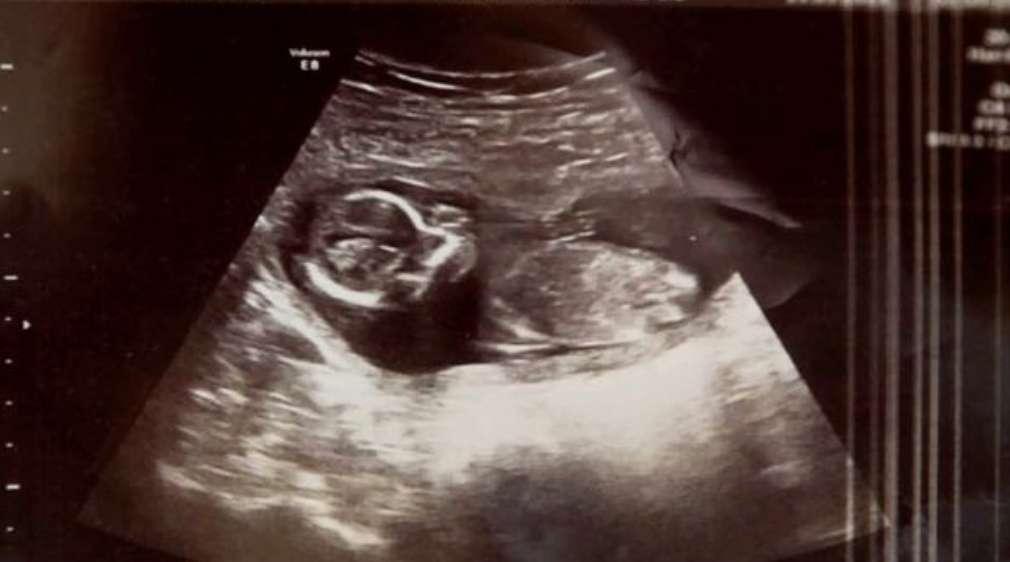

Перед проведенням неприємної процедури лікарі вирішили ще раз зробити УЗД, під час якого виявили серцебиття ще одного немовляти! Мішель була як і раніше вагітна. Так сталось, що спочатку жінка виношувала близнюків, одного з яких втратила на самому початку. Досвідчені лікарі лікарі Ротунди в Дубліні не могли пояснити, як інший малюк міг вижити!

«Лікар вийшов, а потім повернувся зі своїм колегою. Той знову провів УЗД і сказав: «Ви не повірите, але ми чуємо серцебиття!» — розповідає Мішель. — Це була найщасливіша хвилина в моєму житті!». Малюк Меган з’явився на світ і здоровим, чим не на жарт здивув лікарів і своїх батьків.